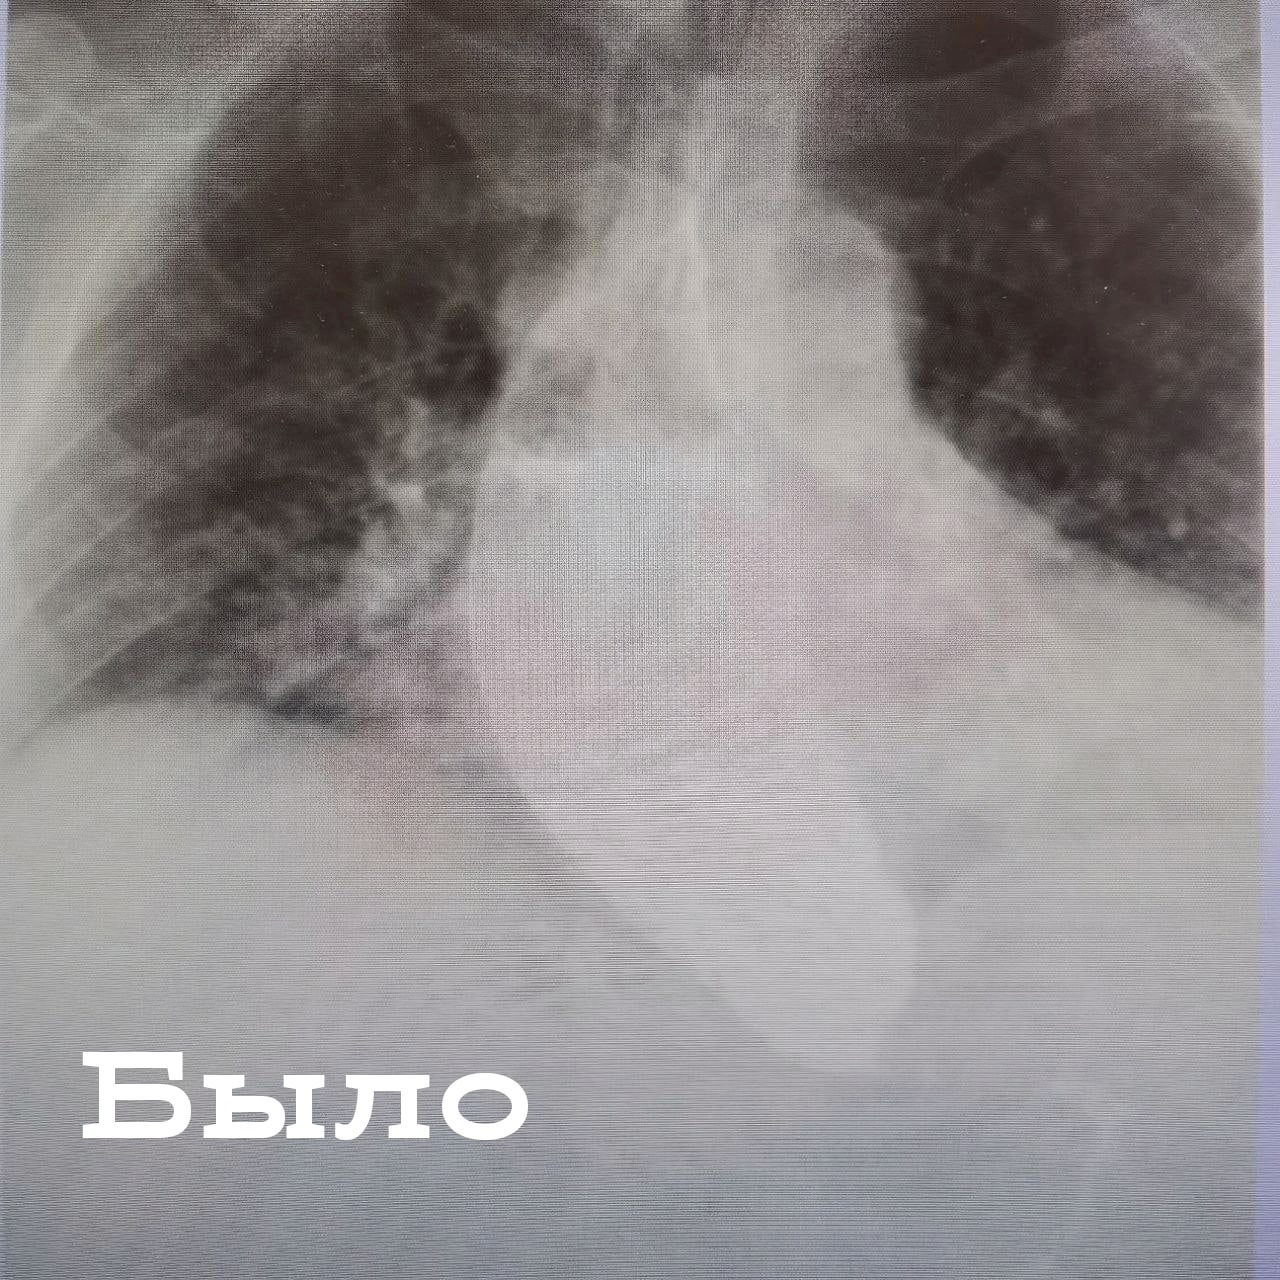

Врачи поставили ей диагноз «ахалазия пищевода». Это нарушение моторной функции пищевода, поражающее мышечный слой органа и нижний пищеводный сфинктер. Из-за спазма мышц пищевода пациент не может нормально питаться. Консервативное лечение при таком диагнозе малоэффективно, а стандартная операция травматична.

«Операция пероральной эндоскопической миотомии позволяет провести лечение максимально щадящим способом, без разрезов, с помощью эндоскопического оборудования. Спазмированный мышечный слой рассекается, а потом снова сшивается правильно. Это позволяет избежать рецидива заболевания. Операция продлилась 1,5 часа и прошла успешно. Уже на 3 сутки после операции пациентка смогла полноценно принимать пищу – как жидкую, так и твердую», – отметил Константин Сысоев.